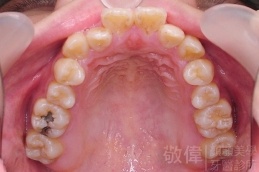

變臉矯正,原來戽斗妹跟大歪臉變成自信正妹

經由本院3D數影X光影像儀分析、與3D齒顎顏矯正技術,再配合口腔顎面正顎專科醫師施以正顎手術治療,雙方共同合作,使患者臉部外觀有很好的改善,大歪變小歪,產生了天南地北的大改變,她的人生也整個變得不一樣。

因為矯正與正顎手術的配合,使「戽斗妹」變成了「陽光正妹」,完全的改變了她的人生,在面對各種場合、與人交際都散發出自信微笑。所以,奉勸家長,如果小朋友有臉顎畸型的問題,應該考慮配合做這種簡單、安全、有效的正顎手術。